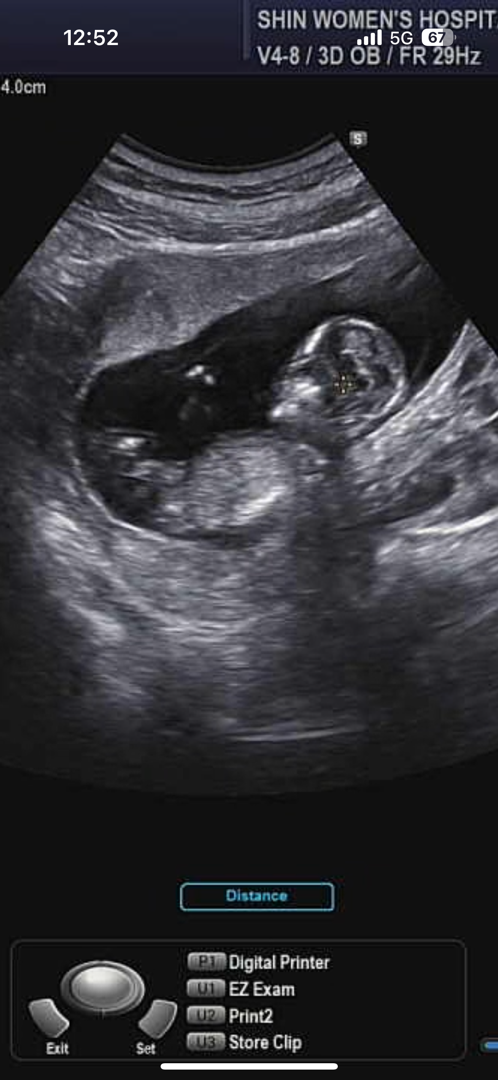

12주 각도 보고 왔어요 궁금해요🥹

아직 생식기는 단정지을 수 없다고 하시는데 입체랑 심장소리만 우렁차게 듣고 왔네요 ㅎㅎ 넘 귀여워요ㅠㅠㅠ 4주 뒤 성별 알 수 있다고 하는데 혹시 동지분들 이 각도로 성별 아실 수 있으신가요???🥹